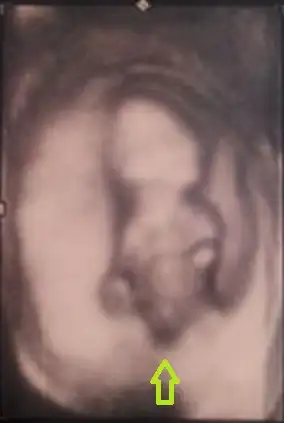

benimde bebişim 12 haftalık..lütfen cinsiyetine yorum alabilirmiyimEki Görüntüle 923096 [/QUO

ya başlık emir kipi gibi olmuş.kusura bakmayın :) merak ediyorum,lüften cevap alabilimiyim..

bunlardan nub a göre tahmin istiyorum kızlar

bunlarda 4d bi çıkıntı var ama göbek kordonumu değilmi yoksa kızda bizmi yanlış yoruyoruz karar veremedik

Erkek bu erkek annesi bence